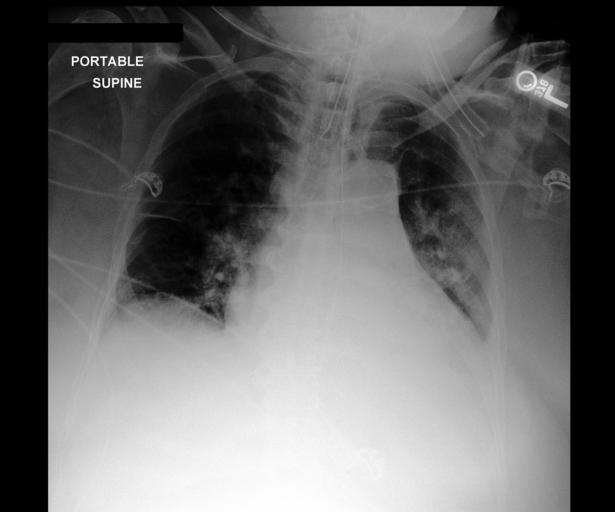

5 Examples

Figure 1 reproduces the example101010In this section we show the JPEG versions of images as released in MIMIC-CXR-JPG (Johnson et al., 2019c). However, as described in Section 3, MAIRA-1 ingests images derived from the original DICOMs. shown in Tu et al. (2023), comparing the output of MAIRA-1 with the best Med-PaLM M variant (84B) and the closest by model size (12B). For illustration, we also include the output of models not trained on the findings generation task (LLaVA-1.5 and LLaVA-Med).

Refer to caption

Original report

INDICATION: _-year-old male with intubation. No prior examinations for comparison.

FINDINGS: Endotracheal tube terminates 6 cm from the carina. Nasogastric tube loops within the stomach, with side port within the gastric body. There are no significant pleural effusions or pneumothorax. Mild retrocardiac atelectasis is present. Heart size is normal. The aorta is tortuous.

Model

Generated findings

MAIRA-1

Endotracheal tube terminates 5 cm above the carina. Nasogastric tube loops in the stomach, with side port near the GE junction. Heart size is normal. Aorta is tortuous and unfolded. There are no pleural effusions or pneumothorax. Lungs are clear. [No comment about atelectasis.]

Med-PaLM M-12B

An endotracheal tube terminates 5 cm above the carina. There is no pneumothorax or large pleural effusion. Opacities in the medial right lower lobe and retrocardiac region may represent atelectasis aspiration or pneumonia. A calcified lymph node is noted in the aortopulmonary window. Cardiac size is normal. [No comment about NG/OG tube.]

Med-PaLM M-84B

Endotracheal tube terminates 5 cm above the carina. Nasogastric tube courses below the diaphragm and inferiorly beyond the film. There is retrocardiac opacity which may represent atelectasis or aspiration. The heart size is normal. The aorta is tortuous and unfolded. No pleural effusions or pneumothorax.

LLaVA-Med The image is a chest X-ray taken on day 1 post-admission. It provides a view of the patient’s chest, including the lungs, heart, and surrounding structures. Chest X-rays are commonly used to help diagnose and monitor various conditions affecting the respiratory and cardiovascular systems, such as infections, fluid accumulation, or structural abnormalities.

LLaVA-1.5

The image displays a close-up view of a human body, focusing on the chest area. The chest is filled with various medical instruments, including a heart monitor and a defibrillator. The heart monitor is placed on the left side of the chest, while the defibrillator is positioned on the right side.

In addition to the medical instruments, there are several wires and cords scattered throughout the scene. Some of these wires are attached to the medical devices, while others are likely part of the electrical connections for the instruments. The presence of these wires and cords suggests that the medical equipment is in use, possibly for monitoring or treating a patient.

Figure 1: Model outputs on the sample from Tu et al. (2023). MAIRA-1 and Med-PaLM M-84B produce similar reports with different errors; MAIRA-1 misses the retrocardiac atelectasis and incorrectly locates the side port of the nasogastric tube, whereas Med-PaLM M-84B incorrectly describes the NG tube as ending beyond the film. For comparison purposes, we include Med-PaLM M-12B, which hallucinates a calcified lymph node and fails to mention the NG tube, and the outputs from LLaVA-Med and LLaVA-1.5, which do not produce realistic radiology reports.